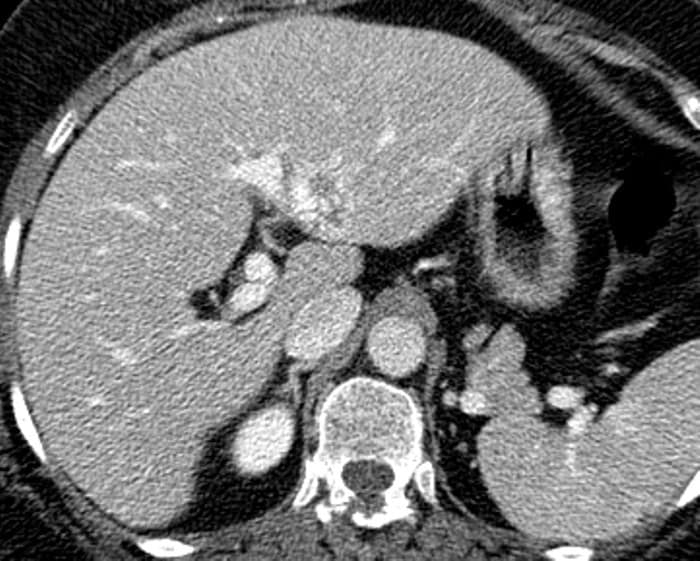

Ung thư đường mật

» Thông tin: Nữ giới – 56 tuổi.

» Lâm sàng: Viêm gan C.